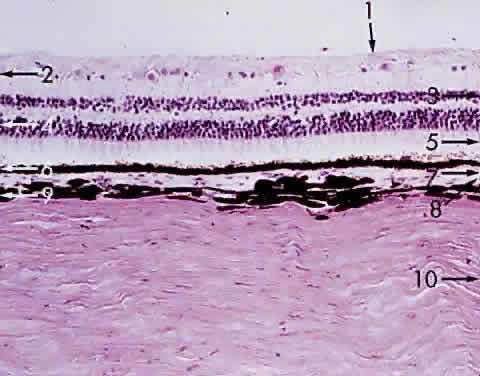

The choroid is a thin (0.2-mm), spongy, pigmented, vascular lamina. It is located between the sclera and the retina, extending from the ora serrata to the optic nerve (Fig. 15). Sensitive ultrasonographic techniques may detect increased thickness of the choroid as manifested by inflammation and neoplasms, focal or diffuse. Chromatophores are scattered within the choroid. The amount of pigmentation of the choroid determines the color of the fundus. Because the retina is transparent except for the blood vessels and the retinal pigmented epithelium (RPE), the variation in pigment accumulation within the choroid and retina determines the clinical picture of the ocular fundus. A heavily pigmented (negroid) fundus has the characteristic dark gray-green reflex, whereas a “blond” fundus has relatively little pigment and the pink choroidal vessel pattern is easily visible. Fluorescein and indocyanine green dye angiography readily provides clinicians with a means of evaluating the vascular integrity of the choroid and the changes that occur with disease. Also, the density of the choroidal pigmentation may affect the degree of retinal burn during photocoagulation of neovascular membranes.

Fig. 15. Choroid wedged between the retina and sclera: 1, internal limiting membrane of retina; 2, ganglion cell layer of retina; 3, bipolar cell layer of retina; 4, nuclei of rods and cones; 5, rod and cone layer of retina; 6, pigment epithelium of retina; 7, Bruch's membrane; 8, choriocapillaris; 9, large blood vessel of choroid; 10, sclera (× 225, KEI 8982B).

The primary function of the choroid is to supply nutrition to the rod and cone layer of the retina. Because of the erectile potential of the vascular channels, the choroid may also have a role in regulating intraocular pressure and in acting as a heat diffuser to protect the photoreceptors from the heating effect of absorbed light, particularly at the macula. At the optic disc, the choroidal circulation joins with the short posterior ciliary vessels and the branches from the central retinal artery to supply nutrition to the optic nerve. As a feature of glaucoma, choroidal peripapillary atrophy is a frequent hallmark. Embryologically, the choroid is derived from the mesoderm that surrounds the posterior portion of the primitive cup. The choroidal bond of Bruch's membrane to the pigmented epithelium of the retina is strong, so in “true” retinal detachments the line of cleavage is between the rod and cone layer and the pigmented epithelium.